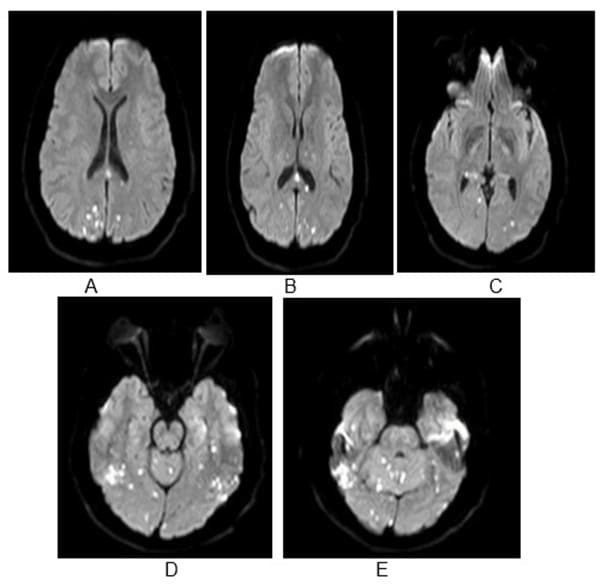

Figure 2A-E: MRI Brain – Diffusion sequence showing bilateral punctate restricted diffusion; A and B - parietal and occipital infarcts, B-E - Occipital infarcts, D and E – bilateral cerebellar infarcts.

Figure 3: Shows corresponding ADC sequences showing hypointense/ darker regions suggesting acute ischemic infarcts.

We present the case of a 30-year-old previously healthy man who presented to the ER on a Sunday morning with acute onset difficulty breathing and weakness in his extremities. He spent most of Friday and Saturday with friends. Earlier that morning he had complained of neck pain and tingling in his hands, which prompted his roommate to bring him to the ER. He was able to walk into the ER, soon after he required assistance to stand up. He now reported, “I can’t move” and “I can’t breathe, I want oxygen”. This was followed by agitation, respiratory distress (Oxygen saturation at 31%) requiring intubation and mechanical ventilation. There was no history of trauma, recent surgical procedures, diabetes, hypertension, heart disease, other significant past medical conditions, and no recent travel history. His vital signs showed normothermia soon followed by hypothermia returning to normothermia (98-degree F; dropping to 94-degree F and 98-degree F over 3 hours), BP 160/98 (then 116/61; followed by 56 mm Hg systolic that improved with fluid boluses. Heart rate was 66/min and later 36/min improving to 80s (36-137 range); EKG showed alternating sinus rhythm and atrial fibrillation with rapid ventricular rate. On day 2 patient failed extubation due to very low tidal volume (80 ml). Chest CT did not show any pathology to explain respiratory failure. His exam revealed quadriplegia and this led to a neurology consultation. Neurological examination showed intact consciousness; he responded to loud verbal and physical stimulation with nods or head shaking. Eye movements initially showed dysconjugate gaze (this resolved in 24 hours), patient exhibited flaccid (0/5) quadriplegia, areflexia and down-going plantar response. He however managed to dislodge the endotracheal tube (ETT) with his tongue movements multiple times. He had normal sensation in his face; below his neck, he had decreased sensation to temperature and pain, but intact light touch and proprioception. Head CT did not show any acute abnormalities. Other investigations on admission revealed normal CBC, CMP; urine drug screen was positive for THC and negative for stimulants, blood EtOH level was < 3. Additional tests included CSF analysis with cell count of 7, normal protein and glucose. CSF culture later came back negative, and he had a normal sed rate (ESR). Brain MRI revealed numerous subcentimeter bilateral cerebellar, posterior temporal and occipital embolic infarcts (Figure 2 A- 2E and Figure 3). Magnetic Resonance Imaging of the cervical spine showed T2 hyperintensity in the territory of the anterior spinal artery extending from C2 to C6 (Figure 1). MRA of the head and neck were normal (Figure 4A and 4B). Transthoracic Echocardiography showed normal ejection fraction, no intracardiac structural abnormalities and no right to left shunt. Transesophageal echocardiography did not reveal any abnormalities in the proximal aorta. CT angiography of head and neck done few days later was normal as well indicating no occlusions or dissections (Figure 5A-5E). He received 1-gram intravenous solumedrol daily for five days based on initial cervical MRI findings in addition to aspirin started after MRI showed acute infarcts. His CSF also showed 14 oligo clonal bands (unclear significance likely secondary to acute ischemia). Hospital course – On day 3 he went into neurogenic shock and multiple episodes of vasovagal bradycardia (HR in the 40s) and demonstrated hemodynamic instability when he was being moved by nursing staff. His exam now showed intact cognition and normal cranial nerve examination. He developed ileus and had frequent episodes of bradycardia (Figure 6), fluctuating blood pressure all part of autonomic dysfunction causing the nurses to panic. He required transvenous pacemaker which was soon replaced with permanent pacemaker. After four weeks his tidal volume improved from 80 ml to 240 ml., he started to regain significant strength in his lower extremities to the point where he was able to stand up and walk up to 25 feet when his vital signs permitted. His upper extremities remained flaccid, areflexic except for his ability to close his hands to gently squeeze a soft ball. Repeat labs including spinal fluid showed similar findings including 14-oligoclonal bands, normal cell count, protein, and glucose. West Nile virus IgM, HTLV-1, HIV, HSV and CSF VDRL testing were all-negative. After eight weeks, his autonomic instability continued to improve and so did his participation in physical therapy sessions. He could now ambulate up to 100 feet using a special walker; however, he remained flaccid in his upper extremities and continued to need intermittent daily ventilator support due to tidal volume at ~300ml. Repeat MRI of his brain and spinal cord was placed on hold due to his pacemaker that requires many weeks for lead maturation.